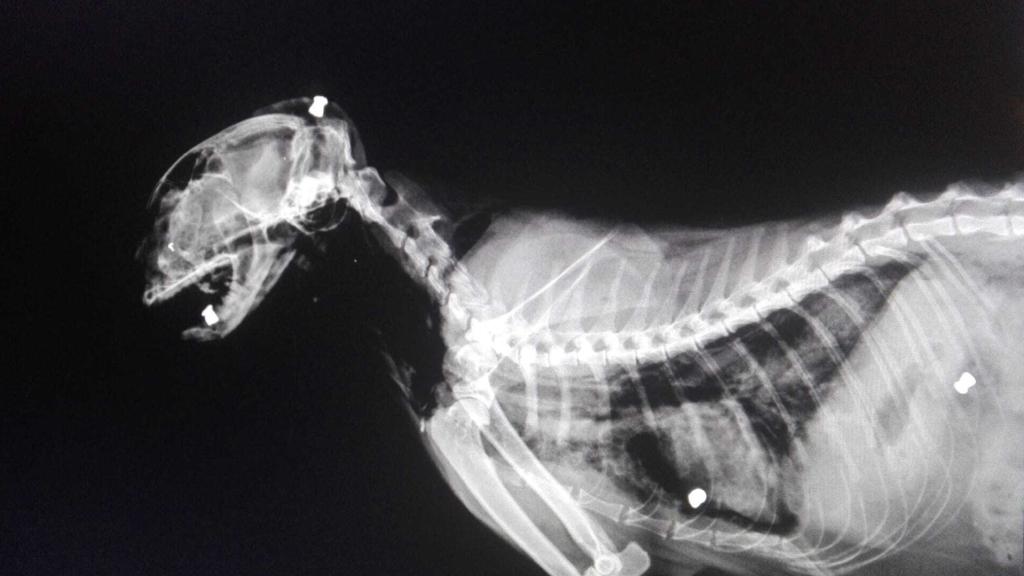

Radiografía de uno de los gatos de María Gil. En ella se observan algunos de los perdigones disparados.

Radiografía de uno de los gatos de María Gil. En ella se observan algunos de los perdigones disparados. A. L.

María la llevó al veterinario y pidió que se le hiciera una radiografía. El animal estaba lleno de perdigonazos. La mujer, de inmediato, llamó a una amiga para que visionara el contenido de las grabaciones de las dos cámaras de fototrampeo que había comprado por 35 euros cada una y que había instalado en la parcela para saber qué estaba ocurriendo realmente cuando ella no estaba allí.